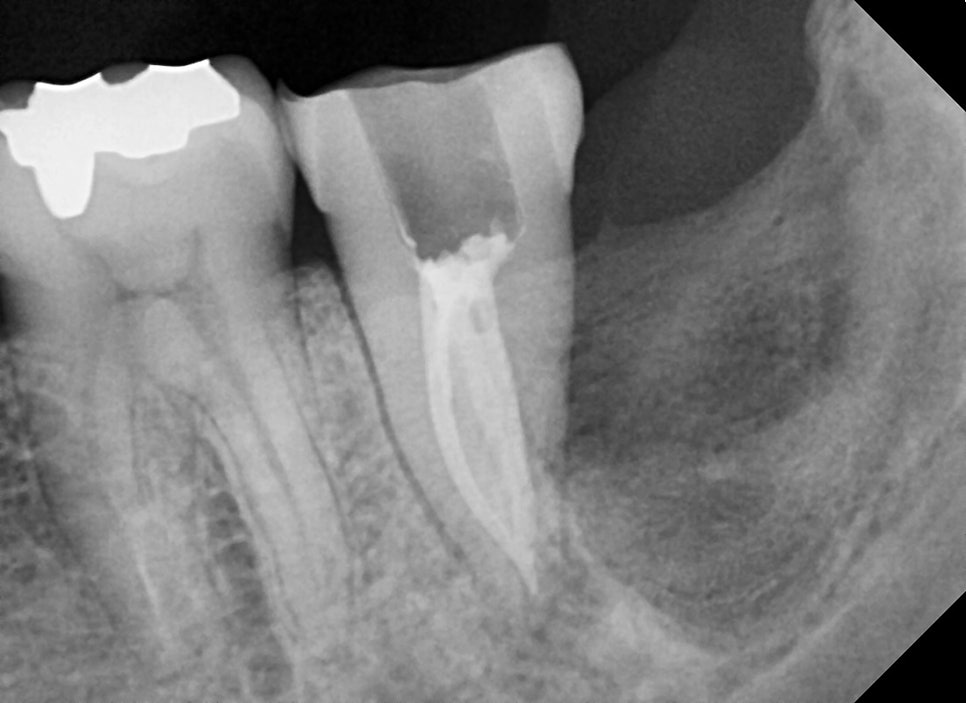

엑스레이 상 뿌리끝에 염증 소견이 보입니다.

이미 크랙이 진행되어 있지만 증상 자체가 심하지 않기에 신경치료하고 증상을 지켜보기로 했습니다.

다행히 신경관을 다 확보한후 신경치료가 끝난 사진입니다.

다른 치아들과는 다르게 뿌리끝이 모아져있는 것을 볼 수 있습니다.

뒤쪽의 사랑니 발치 부위가 커서 일시적으로 동요도가 일어나고 있지만

저작시 통증이 조절된다면 현재 치아를 조금 더 유지할 수 있을 거라고 생각이 됩니다.